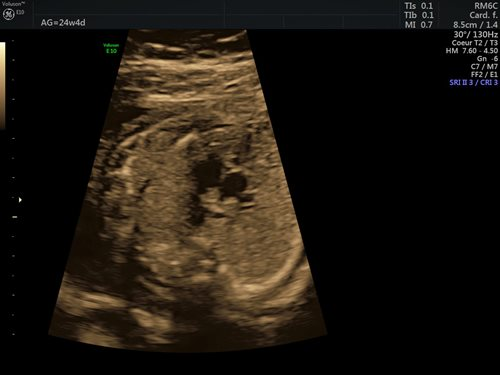

Dans la grande majorité des cas (90 %), l’étiologie des cardiopathies congénitales est multifactorielle, un facteur de risque classique comme des antécédents familiaux au 1er et 2e degré, la présence d’une anomalie chromosomique, d’un diabète maternel de type 1, d’une phénylcétonurie, la prise de certains médicaments ou une infection n’étant pas retrouvé. Pour cette raison, un dépistage systématique par échocardiographie foetale reste indispensable, idéalement entre 18 et 22 semaines de gestation. Le dépistage recommandé consiste en l’obtention d’une vue des 4 cavités cardiaques (fig. 1) et d’une vue des voies d’éjection (fig. 2). (2)

Figures 2